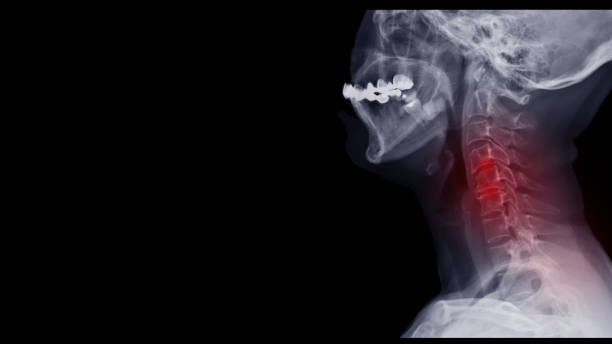

척추협착증은 척추의 추간공이 좁아져 척추 신경이 압박되는 질환입니다.

이로 인해 통증, 저림증, 근력 약화 등의 증상이 나타납니다. 이번 글에서는 척추협착증을 치료하기 위한 다양한 방법을 알려드리겠습니다.